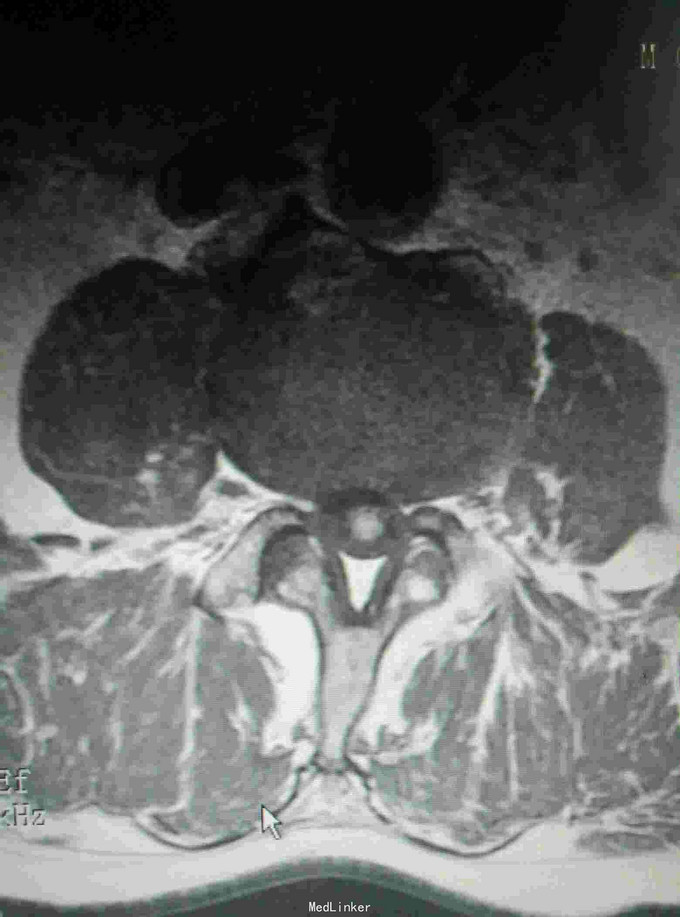

腰痛伴左下肢疼痛不适半月 患者无明显诱因出现腰痛,伴有沿左大腿根部后侧至外踝的疼痛,行走加重,休息可有缓解,期间未做特殊处理,外院核磁提示椎管内肿物,为求进一步诊治入我院。

查体:脊柱生理弯曲存在,腰骶部棘突及椎旁压痛,双下肢肌力IV级,双上肢肌力正常,下肢自主活动无异常,直腿抬高实验阴性,余检查无明显异常。 辅查:核磁提示L3-4椎管内肿物,L4-5椎间盘突出

诊断:椎管内良性肿瘤,腰椎间盘突出 治疗:椎管内肿物切除+腰椎内固定

随访:术后加强腰背肌锻炼,定期复查。 讨论:患者症状要鉴别是肿物引起的还是椎间盘突出亦或是两者皆有,通过查体和片子更多考虑是肿物引起,术中做了肿物切除,进行内固定,患者术后症状好转也提示术前诊断是正确的。对于腰腿痛手术治疗前一定要明确诊断才能确保术后有较好的效果。